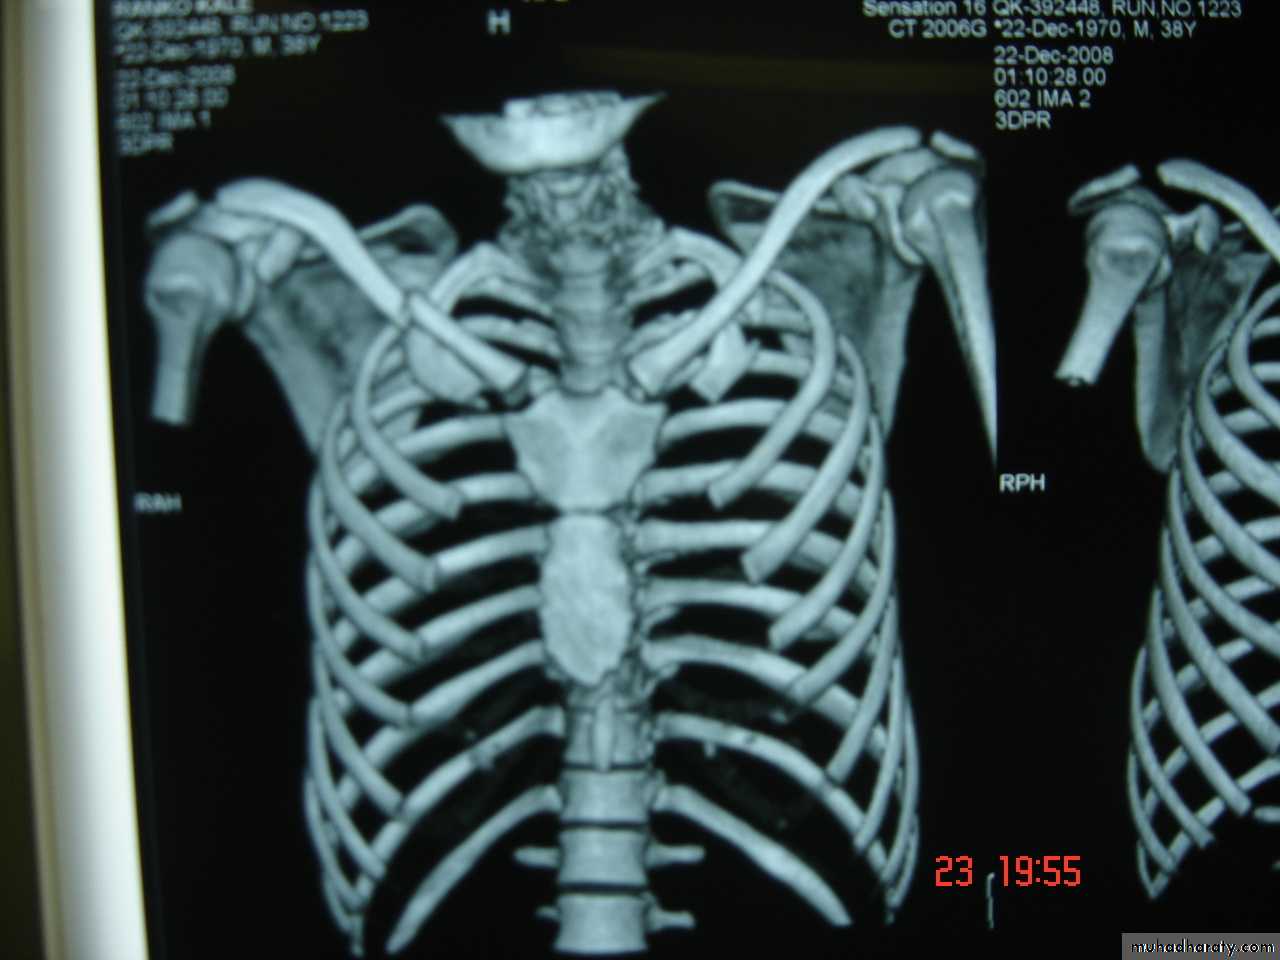

There are (12) pairs of ribs ,

Seven of which are termed (True Ribs) as the cartilages articulate with the sternum.

The lower 3 ribs are termed (False Ribs) which are not connected directly to the sternum.

The eleventh and the twelfth ribs are termed (Floating Ribs )

Because they are not attached anteriorly .

The sternum is divided into the Manubrium .Body and xiphoid . The clavicle articulates with the sternum and Ist.costal cartilage .Muscles associated with the intercostals space are , The external intercostals ,internal intercostals and transversus thoracic muscles .There are (11) intercostals spaces containing a vein ,an artery and a nerve which course along the lower edge of each rib .